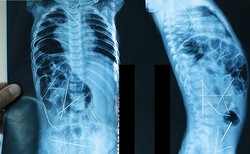

По данным пресс-службы Минздрава страны, мать Азизбека Болтабаева обратилась в медучреждение после плохого самочувствия и поведения ребенка. В первых исследованиях ему был поставлен диагноз воспаление из-за опухшего горла и температуры. Однако после отсутствия улучшения состояния, мальчику провели рентген, и в его теле обнаружены иголки. Младенец и мать срочно были отправлены в Республиканский научный центр экстренной медицины.

17 января он был прооперирован. В девятичасовой операции участвовали почти 10 врачей, из тела ребенка извлечены 13 иголок.

Пока нет точной информации, как иглы оказались на теле мальчика. Врачи отмечают, что 11-месячный ребенок никогда не проглотит столько металла, к тому же в его организме не обнаружены следы травм.